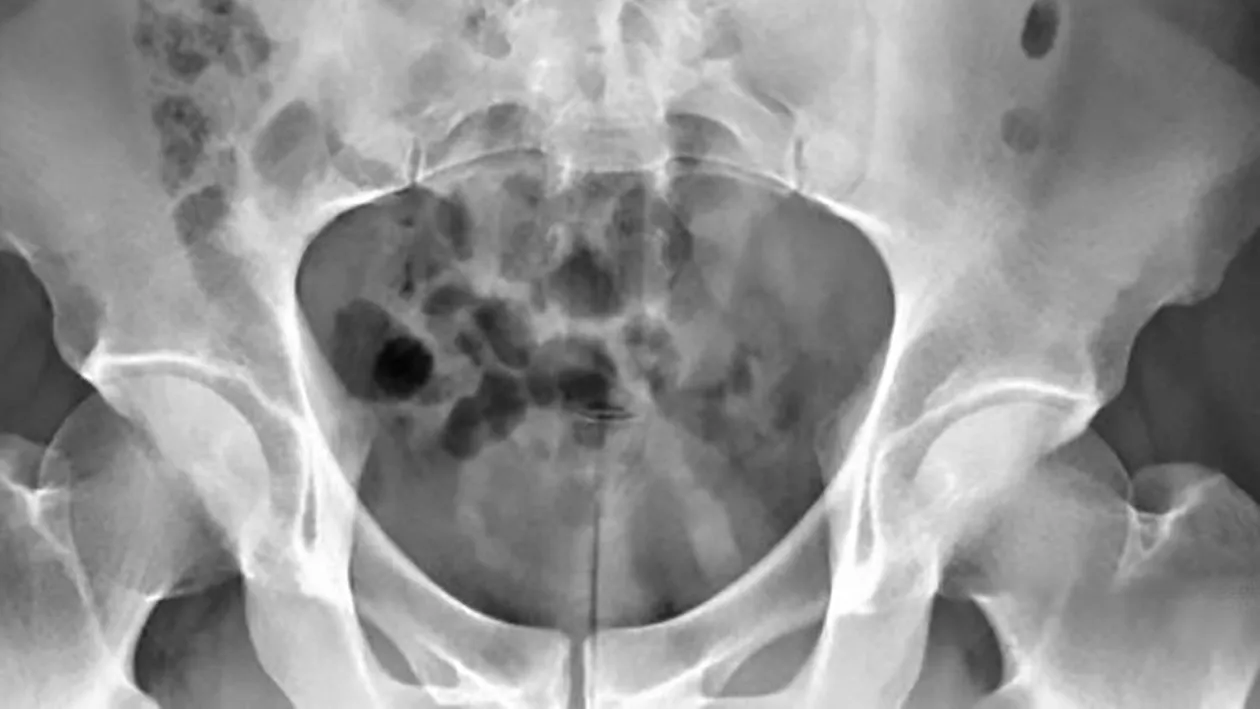

După ce i s-a făcut o radiografie, doctorii au observat obiectul de plastic care a rămas în uretra bărbatului, după ce acesta a folosit jucăria sexuală de 20 centimetri “ca să ajungă pe culmile plăcerii”. După ce aceasta i s-a blocat în “comoara” dintre picioare, bărbatul a stat așa timp de mai bine de 48 de ore, iar când a început să urineze cu sânge, a mers la spital, potrivit jurnaliștilor de la Mirror.

Ajuns în cabinetul unui medic, pacientul i-a spus adevărul. Jiann Bang-bing, șeful Secției de Urologie de la spitalul Kaohsiung Veterans din Kaohsiung, a declarat că obiectul de plastic avea o lungime de 20 de centimetri și o grosime de un centimetru.